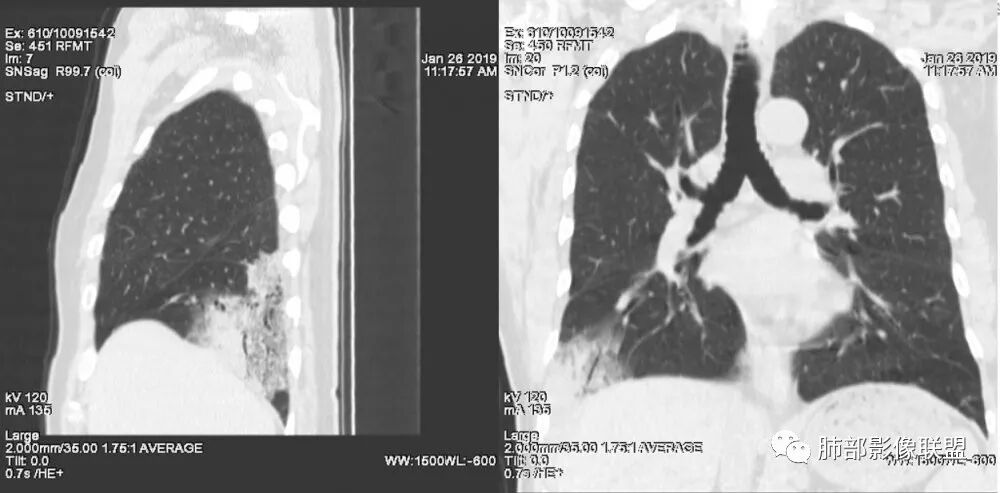

老年女性,右肺下叶沿胸膜下大片状高密度影,外周磨玻璃影,边界较清,内可见蜂窝征及支气管充气征,考虑肺炎型肺癌。

老年女性,咳嗽咳痰病史,右肺下叶大片磨玻璃实变影,胸膜下分布,支气管进入后扩张、僵直,磨玻璃影边界清楚,考虑粘液腺癌。鉴别肺炎。

右肺下叶基底段靠胸膜实变/磨玻璃混杂密度影,边界清楚,内见多发空泡(蜂窝样趋势改变?); 临床:咳嗽咳痰,无发热、胸痛; 考虑腺癌:无发热,感染性病变不首先考虑;部分层面形态类楔形,鉴别肺栓塞

患者中年女性,咳嗽咳痰就诊。胸部CT:右肺下叶后基底段片状实变影,由胸膜向内发展呈扇形,病灶里有小叶内间质增厚、蜂窝状影,周围边界清楚GGO,内可见扩张支气管,淋巴结无明显肿大。综合符合粘液腺癌。

老年女性;右下肺混合实变影,呈楔形改变,边缘清晰,支气管进入且扩张,蜂窝状改变,考虑粘膜相关淋巴瘤,鉴别粘液腺癌,肺栓塞。

老年女性,咳嗽、咳痰。右肺下叶沿胸膜下大片状高密度影,外周磨玻璃影,边界较清,小空泡,蜂窝征及支气管充气征,叶间裂串珠征,考虑:肺炎型肺癌,鉴别:肺克,链球菌,NTM等感染。

右肺下叶胸膜下大片状MGGO,其内结构紊乱,可见空泡征,病灶内近端支气管扩张,远端闭塞,形态不规则,边界部分清楚,部分似清非清,考虑粘液腺癌,鉴别淋巴瘤

1.本例病灶较大片混杂密度影,胸膜下分布为主(未沿着支气管分布),该分布特点可见于大叶性肺炎、干酪性肺炎、淋巴瘤及粘液腺癌等。可惜未提供增强扫描图像。

2.病灶示中央实变区,周围GGO,可见明显小叶间隔增厚,GGO边界清楚,应当考虑到恶性病变的可能性。肺炎因炎性水肿及渗出,影像上边界常模糊不清,注意早期粘液腺癌可出现似清非清的边界。粘液腺癌因粘液成份较多,密度一般偏低,纵隔窗病灶常会消隐或范围会明显缩小,这不同于炎性实变。

3.病灶内支气管走形略显僵直,侧支少(粘液阻塞),也符合肺腺癌的枯树枝征。而大叶性肺炎的支气管是管壁光整、通畅、自然,结核的支气管常常壁增厚,甚至狭窄后扩张;